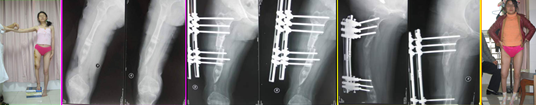

病例1:张某,女,14岁,化脓性骨髓炎后遗留缺损性骨不连,骨缺损约2.5 cm,肢体短缩约16.4 cm,膝关节强直,面临截肢。